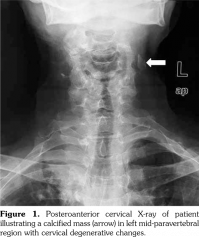

An 80-year-old female patient was examined due to complaint of neck pain over the last year which has aggravated recently. She denied history of trauma. Her medical history indicated that she was taking some medications for hypertension and coronary artery disease. Physical examination was compatible with cervical osteoarthritis with limited cervical range of motion in all directions and tenderness to palpation. Laboratory findings including complete blood count, erythrocyte sedimentation rate, C-reactive protein, serum calcium, phosphorus, parathyroid hormone, and vitamin D levels were within normal ranges. On radiological evaluation, cervical X-ray revealed a calcified mass in the left mid-paravertebral region with cervical degenerative changes (Figure 1). At first glance, a calcification inside the cervical muscles was suspected. Ultrasonographic examination of the cervical region revealed the presence of intraluminal calcification at the level of the bifurcation of the left common carotid artery (Figure 2a-c). The patient was referred to neurology department for being at risk for stroke.

Carotid arteries are the major vascular structures that deliver blood to brain. A blockage in carotid arteries can lead to stroke which is typically caused by atherosclerosis.(1) The artery-wall thickens as a result of invasion and deposit of white blood cells and proliferation of intimalsmooth-muscle cell creating a fatty plaque which is known as atherosclerosis.(2) These deposits also contain cellular waste, cholesterol, and triglycerides with often occurring calcification.(2) Therefore, paravertebral calcifications seen on X-ray might be inside the vessels, particularly in the elderly. Complications of the carotid artery calcification should be kept in mind, so that the patient can be referred to the relevant departments before occurrence of catastrophic consequences such as stroke. Ultrasonography should be the method of choice in confirming the diagnosis.(3)

Lastly, ultrasound gives not only an opportunity to evaluate musculoskeletal pathologies, but also offers visualization of a wide range of nearby tissues such as vessels and organs. Physicians who are dealing with musculoskeletal conditions and performing ultrasound should conduct a thorough musculoskeletal ultrasound examination including nearby vessels.